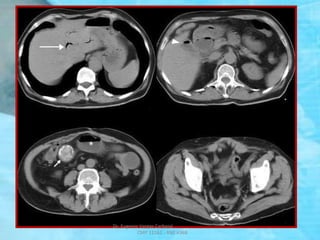

TAC: TBC ILEO CECAL

(ENGROSAMIENTO DE LA PARED DEL

ILEO DISTAL y CIEGO – ADENOPATIAS)